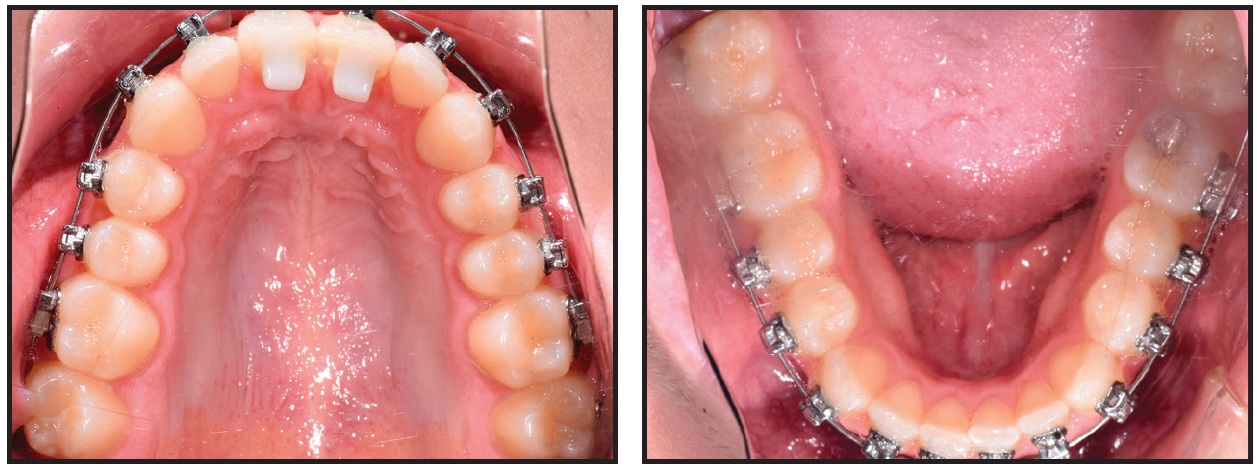

A 12-year-old female presented for treatment of minor crowding, a moderately deep bite, and narrow dental arches (Fig. 9).

Fig. 9 Case 2. 12-year-old female patient with moderate crowding in both arches, upper left lateral incisor and upper right first premolar in crossbite, and Class I molar and Class II canine relationships before treatment.

The examination showed an upper midline shifted 1mm to the left, moderate crowding in both arches, unilateral crossbites of the upper left lateral incisor and upper right first premolar, and lips that were slightly protrusive relative to the E-line. Good facial profile and balance were noted. The upper incisor positions were normal, but the buccal segments were lingually tipped. The patient was diagnosed with bilateral Class I molar and Class II canine relationships.

Our nonextraction treatment plan was to use Insignia* custom braces with anterior bite turbos and SmartArch .016" and .018" × .025" Copper NiTi archwires, followed by .021" × .025" Insignia custom Copper NiTi and .021" × .025" TMA wires. The goals were to level and align the dentition and correct the midline discrepancy.

Fixed appliances were bonded to all teeth in both arches, and .016" SmartArch Copper NiTi wires were placed (Fig. 10). Anterior bite turbos were bonded as in Case 1.

Fig. 10 Case 2. Fixed appliances bonded and .016" SmartArch Copper NiTi wires placed in both arches.

After 10 weeks of treatment, the crowding was resolved, crossbites were corrected, and midlines were coincident, but slight rotations remained (Fig. 11). New .018" × .025" SmartArch Copper NiTi wires were placed in both arches.

Fig. 11 Case 2. After 10 weeks of treatment, 018" × .025" SmartArch Copper NiTi wires placed in both arches.